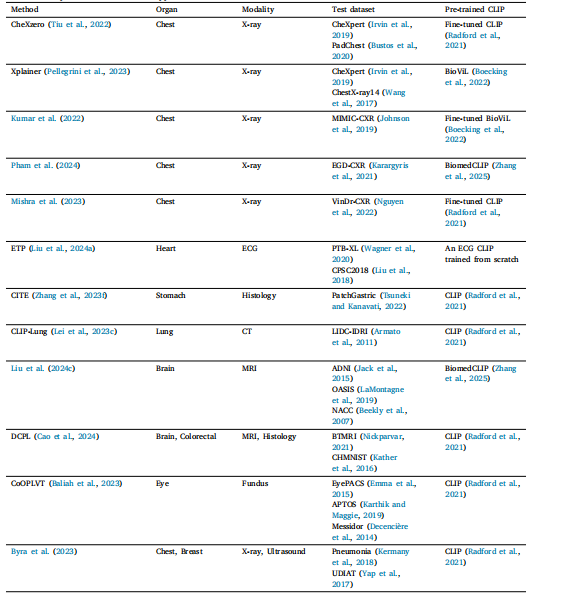

Table 3Overview of representative classification applications.

表3 代表性分类应用概述。